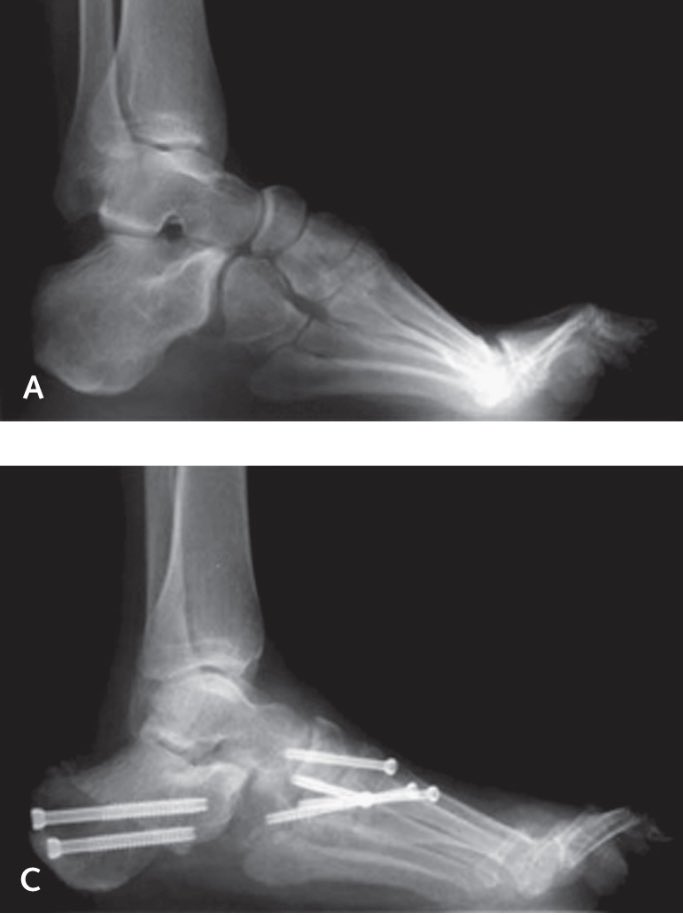

🦴 القدم الجوفاء (ذات القوس العالي):

- قص و تعديل العظام

- تثبيت المفصل في مرحلة متقدمة